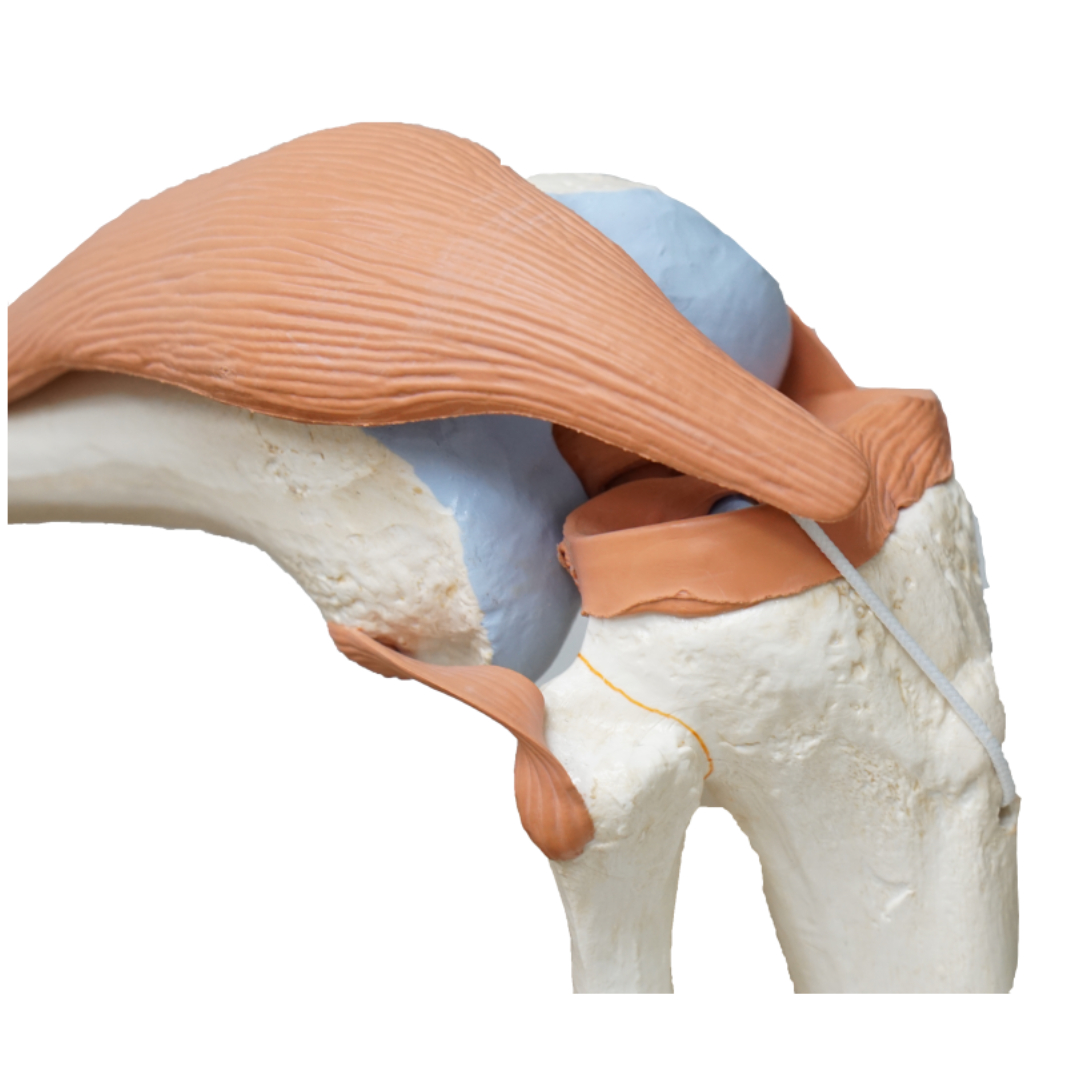

2. 관절의 변형 시작

손가락이나 발가락 같은 작은 관절에서 시작하여, 뼈가 조금씩 변형되기 시작합니다. 이때 손가락이 약간 휘어지거나, 발가락이 비틀 어지 듯한 변형이 관찰될 수 있습니다.

2. 근육 위축

염증이 근육과 인대에도 영향을 미치면서 근육이 위축되고 힘이 약해집니다. 작은 물건을 들거나 간단한 일상 동작을 수행하는 데에도 어려움을 겪습니다.